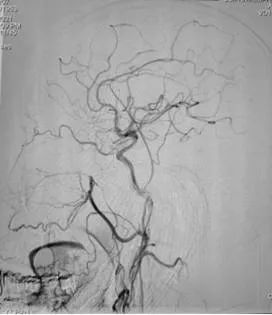

手术过程:术中采取弹簧圈辅助填塞,Onyx液态胶多支供血动脉分次栓塞治疗措施,由于供血动脉纵横交错,手术难道可想而知,经过4小时的艰难努力,于18:30手术结束,术程顺利,成功帮助患者填塞了动静脉瘘,为患者解决了病痛。